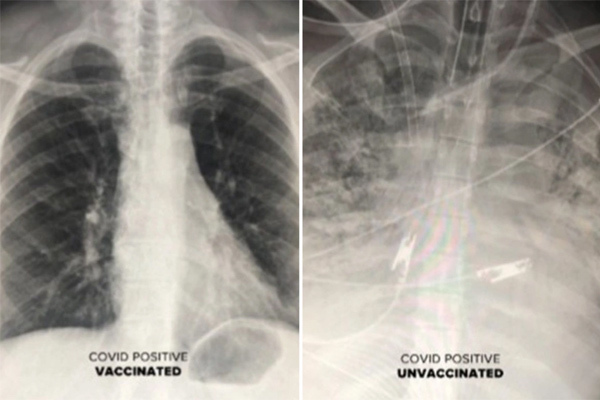

Khác biệt giữa phổi người bệnh Covid-19 đã tiêm vắc xin và chưa tiêm

Phim chụp cho thấy tác động của virus SARS-CoV-2 đối với phổi của những bệnh nhân Covid-19 đã hoặc chưa chủng ngừa.